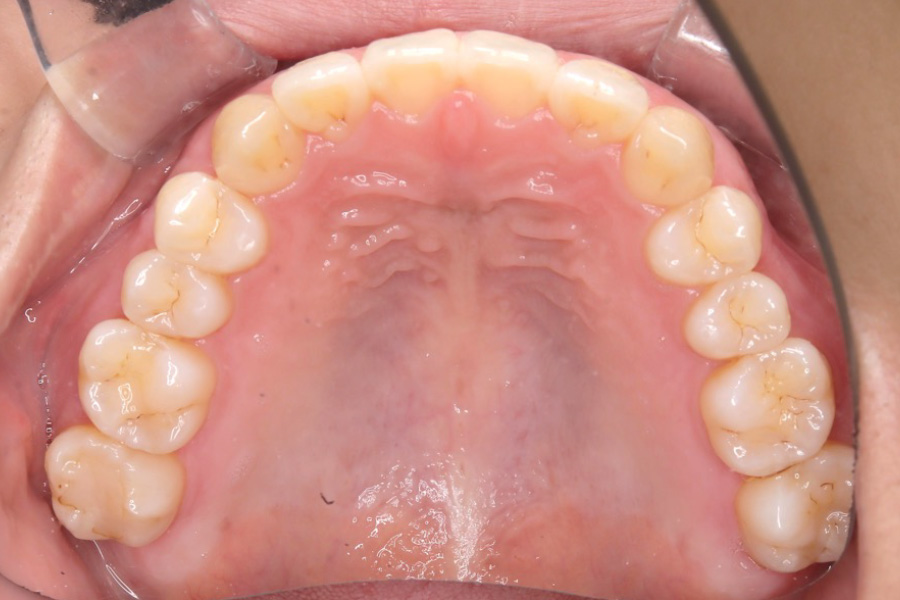

【20代女性】

全体のガタつきを

インビザライン矯正で治療したケース

治療後

主訴 全体のガタつきが気になる

治療内容 インビザライン矯正

非抜歯